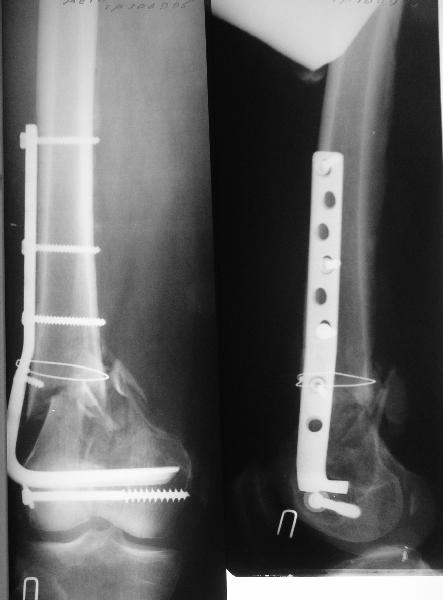

На операцию пошли, имея в возможных планах практически все прозвучавшие предложения - и про пластину, и про аппаратную коррекцию. Была даже несколько экстравагантная идея закрыто убрать винты из диафизарной части пластины, наложить аппарат, постепенно восстановить ось и длину, после чего вновь ввести винты в пластину, подложив шайбы между пластиной и костью.

Удалили ластину без проблем. Выявилась значительная подвижность. В этих условиях сразу пропала мотивация к постепенной коррекции аппаратом. Попробовал восстановить длину, введя между отломками spreader. Отчасти удалось. Тогда защили рану, наложили спицевой дистрактор (2 спицы в дистальный отдел и 1 вверху). после этого был убран и спонгиозный винт. И сделали антгерадное штифтование, как говорится, "по принятой в

клинике методике".

Дополнительные доступы для введения гвоздя и проксимальных винтов понадобились, но они маленькие, по 1 см. Нижние винты ввели прямо между швами. Суставы дополнительно не травмировали, и даже ввели гвоздь не через f. piriformis, а через большой вертел.

Длину восстановили, возможно, даже с изьбытком, ну да динамизируем пораньше. Введенные в овальное отверстие дистальые винты имеют угловую стабильность. Снимки приложены. Заранее спасибо за критику и комментарии.

Довольно симпатично получилось. Не сомневался, что будет именно такой антеградный реостеосинтез.

Была ли педресация на столе после окончательной фиксации? Уверен ли ты, что "угловая стабильность" дистальных винтов позволит агрессивно заниматься разработкой движений в коленном суставе?

Nicely executed surgery with good planning resulting in great looking x-rays but not the best the way to deal with this fracture. Earlier fracture was having slight translation with no angulation and no instability, now ur fracture is distracted with potential instability as your construct is not the best suited to this place, so more likelihood of non union or complications.

Should have preferred a locking plate if at all u wanted to reoperate and

added copious bone graft.